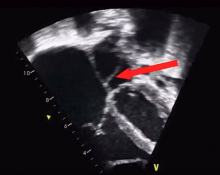

The authors report a procedure performed for a toddler who was misdiagnosed with asthma as an infant. She had progressive respiratory symptoms and was found to have cor triatriatum sinister with a restrictive communication, decompressing vertical vein, severe tricuspid regurgitation, and severe right ventricular dysfunction.

The surgical repair, shown in the video, was uneventful and the right ventricular function was normalized on follow-up echocardiograms.

To the authors' knowledge, this is the first report of cor triatriatum sinister with a restrictive fenestration, a decompressing vertical vein, an intact interatrial septum, and severe tricuspid regurgitation in a toddler. The treatment was successful as demonstrated by the follow-up echocardiograms, which show normalization of the ventricular function and pulmonary artery pressure.